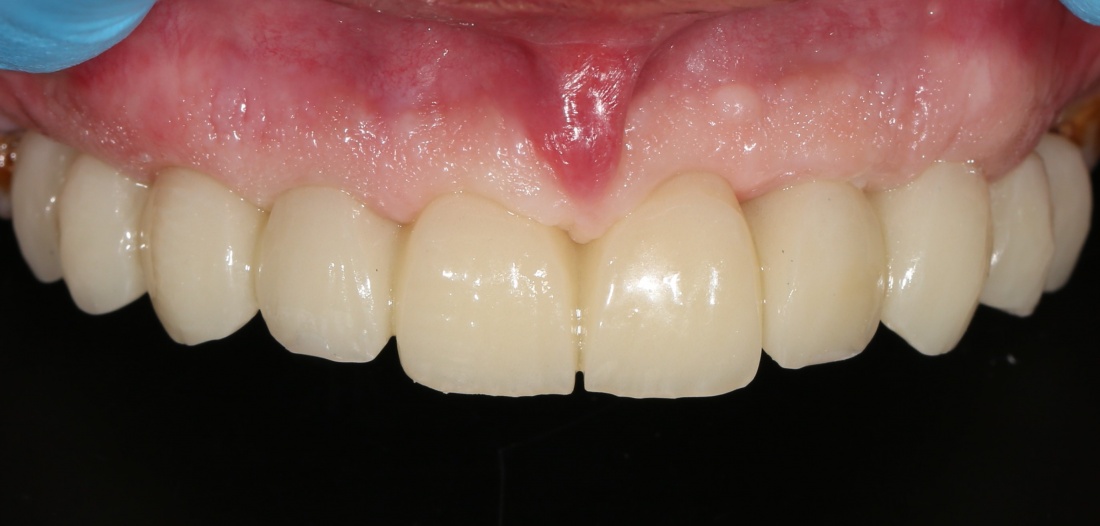

Что мы ему предложим? Разумеется, несъемное протезирование с опорой на 6-8 имплантатов:

Это в большей степени будет удовлетворять его пожеланиям и требованиям. Фактически, он получит новые зубы, только искусственные: